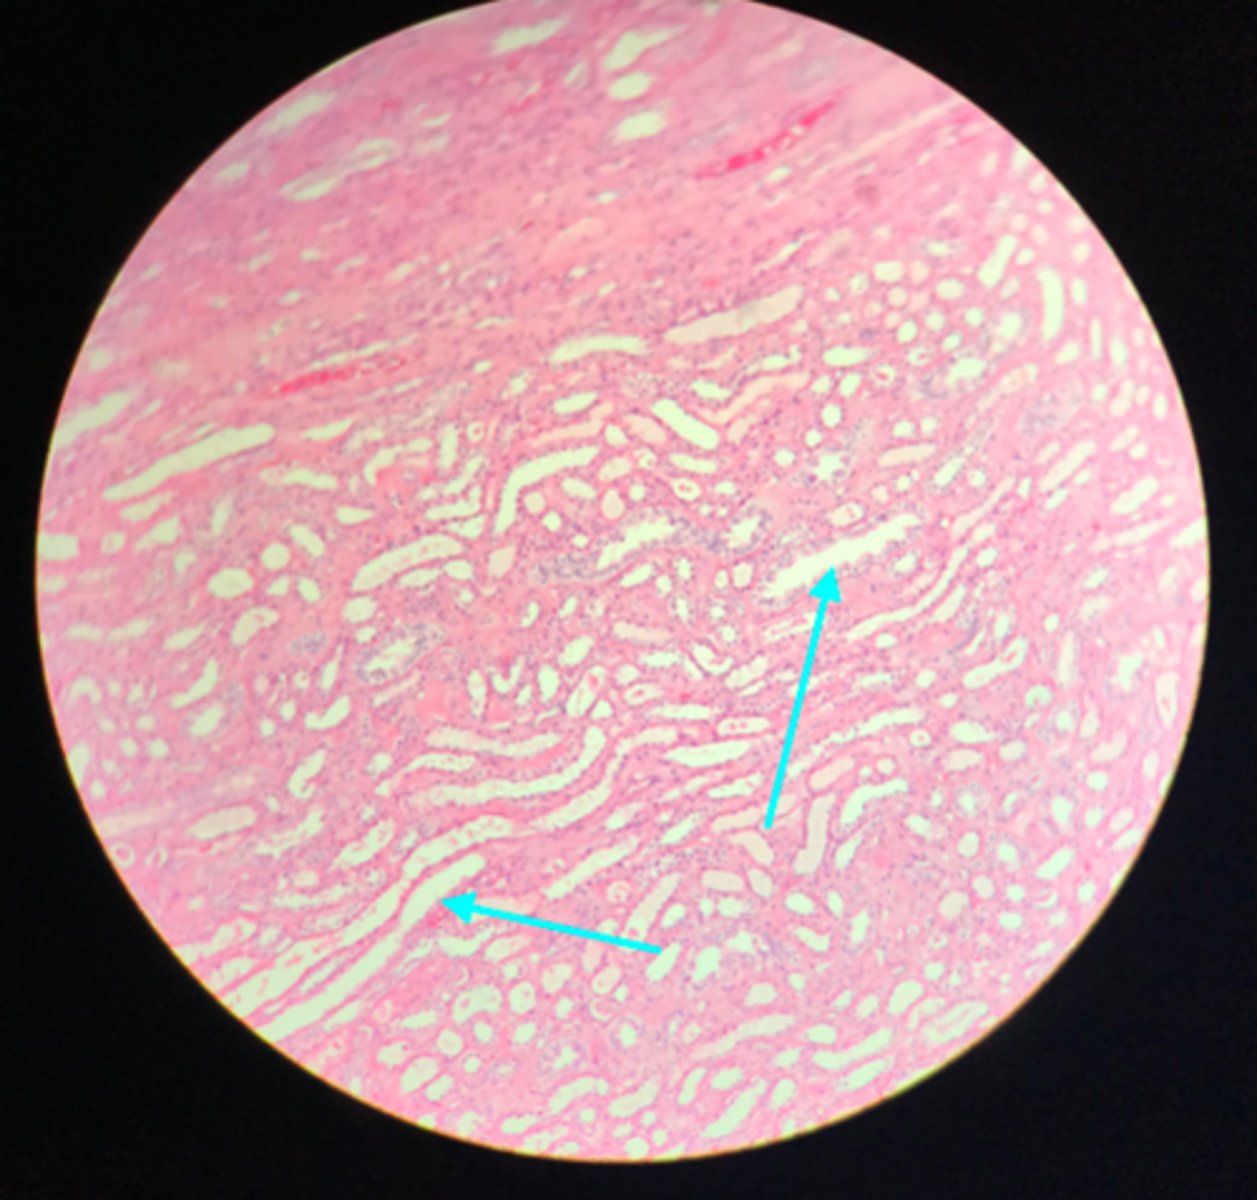

Medulla of the kidney

There are no glomerular corpuscles present and there are numerous visible collecting ducts

What layer of tissue of which organ is depicted on this slide? How can you tell?

Collecting ducts (in the medulla)

What structure of the kidney are the blue arrows pointing at?